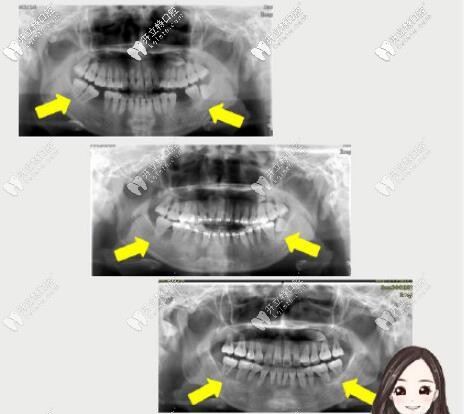

臨床中經(jīng)常遇到一些顧客,一或者第二磨牙大面積齲壞,只剩殘根,而智齒相對(duì)健康此時(shí),通過(guò)正畸的方式近中移動(dòng)智齒代替第三磨牙不失為一種較好的治療方案。

矯正后不但牙齒排齊了,而且左上掉的大牙也用智齒前移代替了,既改善了美觀,又省了一筆種牙的費(fèi)用。

這位顧客主訴沒(méi)下巴。骨性+牙性齙牙、下頜后縮,磨牙缺失咬合已經(jīng)錯(cuò)位。

這時(shí)原本“廢棄”的智齒派上用場(chǎng),第三磨牙前移轉(zhuǎn)正為第二磨牙,參與到咬合關(guān)系當(dāng)中。

拔牙矯正,智齒替磨牙,調(diào)整頜平面,終收獲了現(xiàn)在的面型